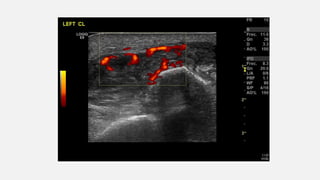

ECOGRAFIA PARTS BLANDES

• Edema i hiperèmia del teixit cel·lular

subcutani a nivell de la cicatriu de la

cara lateral del turmell esquerre.